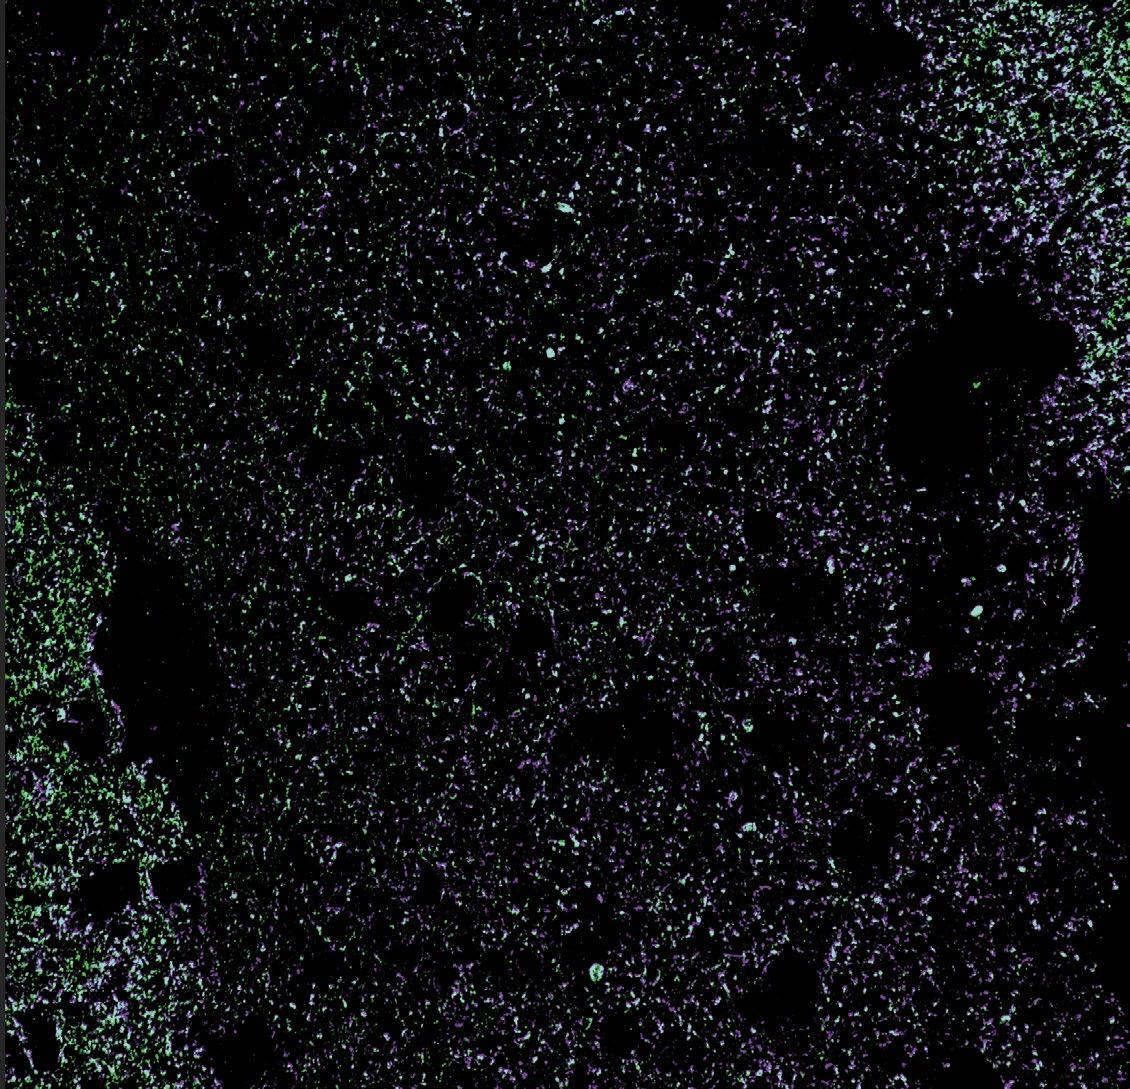

Human schwann cell - derived exosomes negatively stained, imaged under a transmission electron microscope.

Ateam of The Miami Project investigators are working on a novel strategy using human Schwann cells to deliver proteins and genetic materials to the injured nervous system as a new therapeutic intervention. The Miami Project has a rich history of working with Schwann cells, one type of neural support cell that helps wrap the exterior of nerve axons in myelin. In doing so Schwann cells play a structural role analogous to insulation, coating the long cylindrical axons of nerves so that impulses are conducted with greater efficiency, speed, and reliability. Researchers at The Miami Project have known for some time that the structure is not Schwann cells’ only function and are now realizing a novel potential through a bench-to-bedside investigation of Schwann cell-derived exosomes.

Exosomes, a kind of extracellular vesicle, are a way by which cells can transport a rich cargo efficiently between one another. The vesicles, that eventually become spheres packed with molecules, begin their journey in an unassuming manner. The cargo that will eventually fill them is manufactured inside the cell, carefully selected for export, and then moved to the surface of the cell. There, a portion of the cell membrane begins to bud away from the cell, is filled with the cargo in the region, and eventually buds off completely. This process is not specific to one cell type, but the contents of the exosomes do contain a unique payload specific to the cells of origin. Furthermore, their exteriors can be labeled with specific markers that might help them find or act on targets of interest to their parent cell.

In the case of Schwann cells, the natural exosome production by which these cells can exchange information with their surroundings occurs at a modest rate. When optimized in an artificial setting, such as a laboratory culture dish, Schwann cells can be made to extrude great amounts of exosomes. Containing the cell-specific cargo, exosomes might be a viable alternative treatment to delivering the whole cells through invasive transplantation procedures. Whole cells are large, can migrate, and must likely stay alive to enact their effects. Exosomes are smaller, but still contain certain naturally occurring cargo of likely biological relevance.

Furthermore, the assortment of internal contents—proteins, RNA, and other molecules—means exosomes have a variety of immediate and longer lasting potential effectors they might act on, increasing the chance for a positive effect including neuroprotection or regeneration. Importantly, there is scientific evidence in other fields that exosomes from certain cells have therapeutic relevance to conditions involving the tissues where the cells play a role. For example, exosomes released by cancer cells can promote tumor growth and metastasis, while exosomes from immune cells can help to fight infections and modulate immune responses. In this manner, Schwann cells that normally play a structural role inside the body might instead be coerced outside the body into becoming pumps, like tiny autonomous pharmaceutical companies manufacturing a drug to be introduced to the body for treatment of a neurological condition.